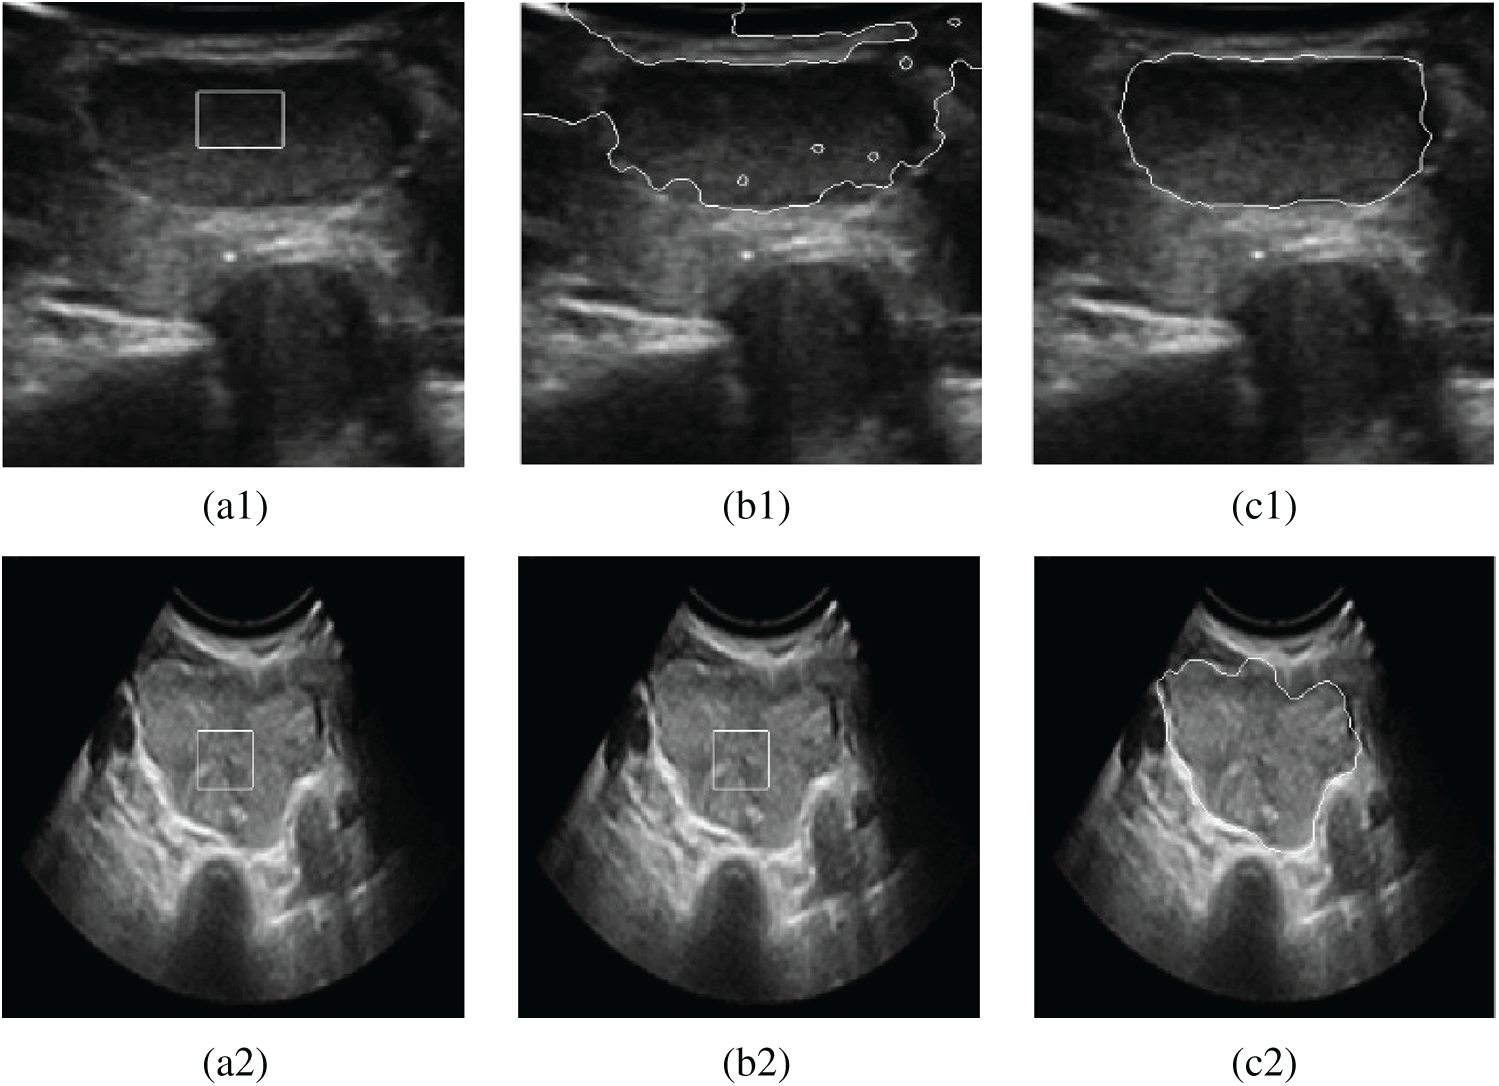

Figure 2: Experimental comparison chart of gradient edge detection and phase detection. (a1) Original image (b1) Gradient edge detection (c1) Phase edge detection (a2) Original image (b2) Gradient edge detection (c2) Phase edge detection

Therefore, a boundary indicator function based on the phase congruency operator and gradient operator is proposed in this paper. Let

In light with the Fig. 3, a 3D comparison of the effects is shown. The comparison is between the original edge-stopping function based on the gradient information and the edge-stopping function combining the phase information with the gradient information for thyroid ultrasound images at the tumor edge. It can be seen that the improved boundary function convergent at the weak boundary.

The descent flow equation is the evolution equation of the level set segmentation model that combines the phase with gradient information. Fig. 4 shows the effect of image segmentation of the above algorithm.

Figure 4: Contrast segmentation results of thyroid ultrasound images. (a1) Original image 1 (b1) DRLSE model (c1) The proposed model (a2) Original image 2 (b2) DRLSE model (c2) The proposed model